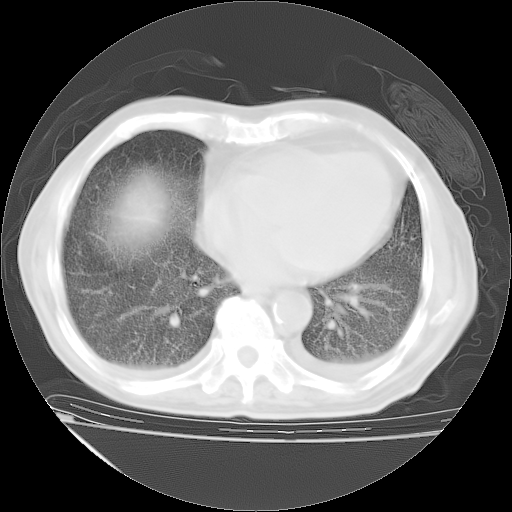

甲强龙80mg/日+抗结核治疗(异烟肼+利福霉素+乙胺丁醇)10天。复查肺部CT。

94186 2 1 .bmp

94186 3 1 .bmp

94186 3 2 .bmp

94186 3 3 .bmp

94186 3 4 .bmp

94186 3 5 .bmp

94186 3 6 .bmp

94186 3 7 .bmp

94186 3 8 .bmp

94186 3 9 .bmp